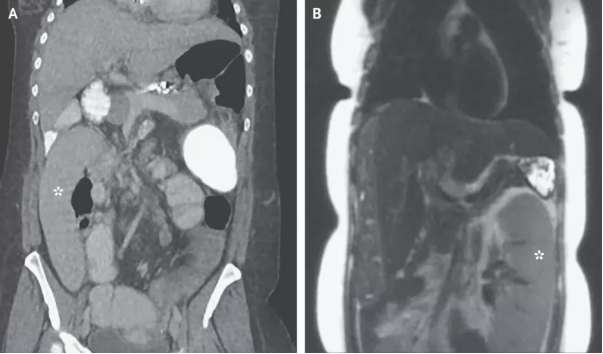

密歇根醫(yī)學(xué)院內(nèi)科醫(yī)生Alexander Wester博士介紹,脾臟是人體內(nèi)負(fù)責(zé)過濾血液并提供免疫力的器官,通常位于腹部左上位置,胃部上方。但是,這名36歲婦女的影像學(xué)結(jié)果顯示,她的脾臟出現(xiàn)在了腹部右下位置。

巧合的是,這名婦女剛剛做了肝癌篩查,影像學(xué)報告中的脾臟還是正常的,位于身體左側(cè)(圖B)。她檢查之后的第一天出現(xiàn)了腹痛和嘔吐,第二天再做一次檢查,脾臟向右跑了0.3米(圖A)。

Wester解釋,這是一種罕見的疾病,稱為“脾臟漂移”。這名婦女患有一種叫做“原發(fā)性硬化性膽管炎” 的肝臟疾病,由于膽管發(fā)炎可造成嚴(yán)重的肝臟疤痕,導(dǎo)致肝硬化,使血液流動能力受阻。血管堵塞導(dǎo)致血液回流,受影響最嚴(yán)重的部位就是脾臟。隨著時間推移,脾臟容納血液增多,變得越來越大,周圍的韌帶被拉伸松弛,使脾臟脫離上腹部的位置,跑到別處去了。